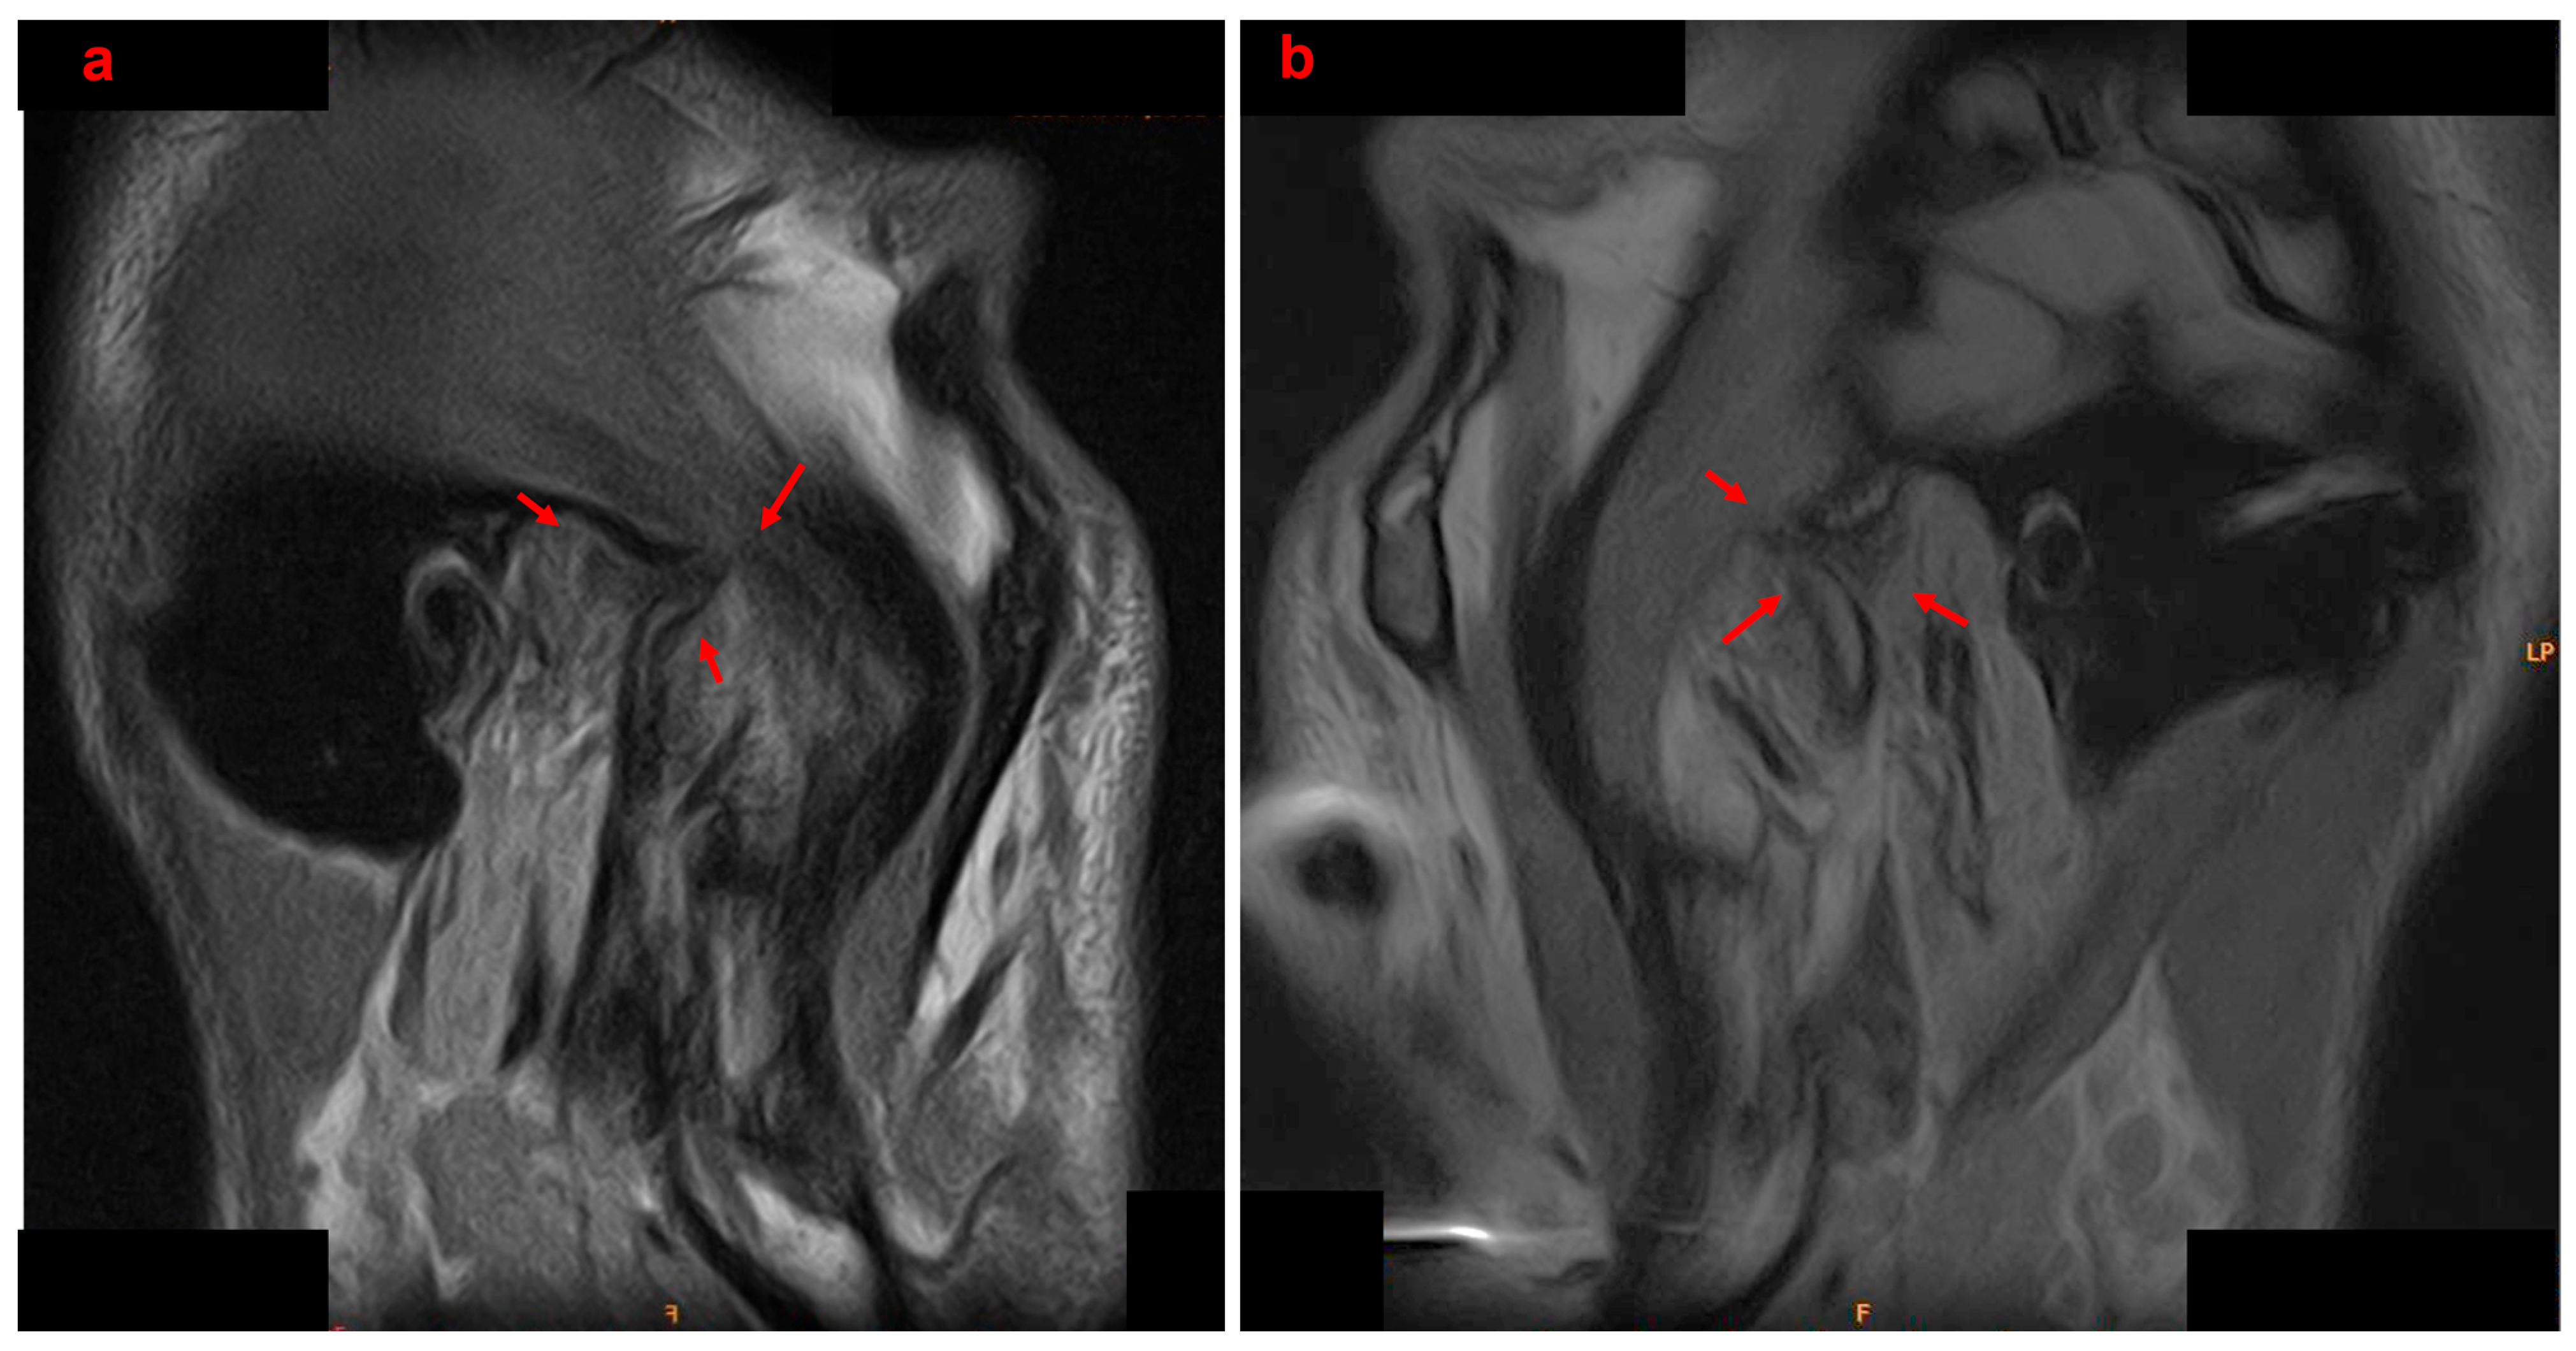

2.4. Diagnosis and Treatment Planning

- Hasan, N.M.A.; Abdelrahman, T.E.F. MRI evaluation of TMJ internal derangement: Degree of anterior disc displacement correlated with other TMJ soft tissue and osseous abnormalities. Egypt. J. Radiol. Nucl. Med. 2014, 45, 735–744. [Google Scholar] [CrossRef]